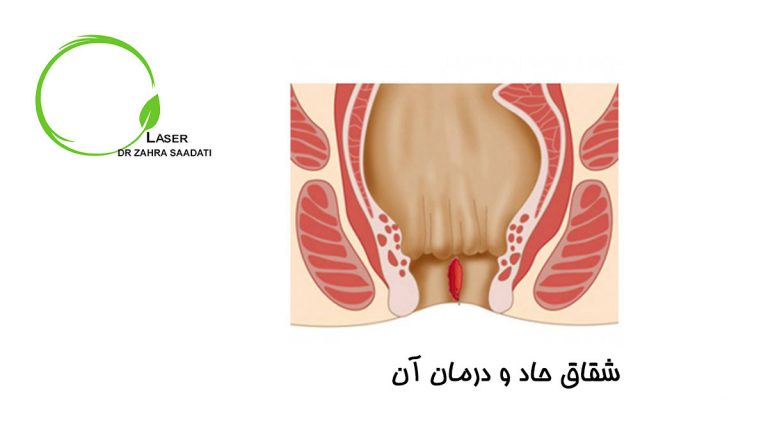

شقاق حاد مقعد یک وضعیت دردناک است که وضعیت سلامت تعداد قابل توجهی از جمعیت مردم را تحت تاثیر قرار…